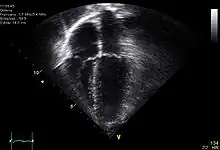

Echocardiogram is a study in which an ultrasound is used to exam the function of the heart. In Traumatic cardiac arrest, an echocardiogram may show ineffective motion of the heart and may provide clues that point to a specific cause of the arrest.